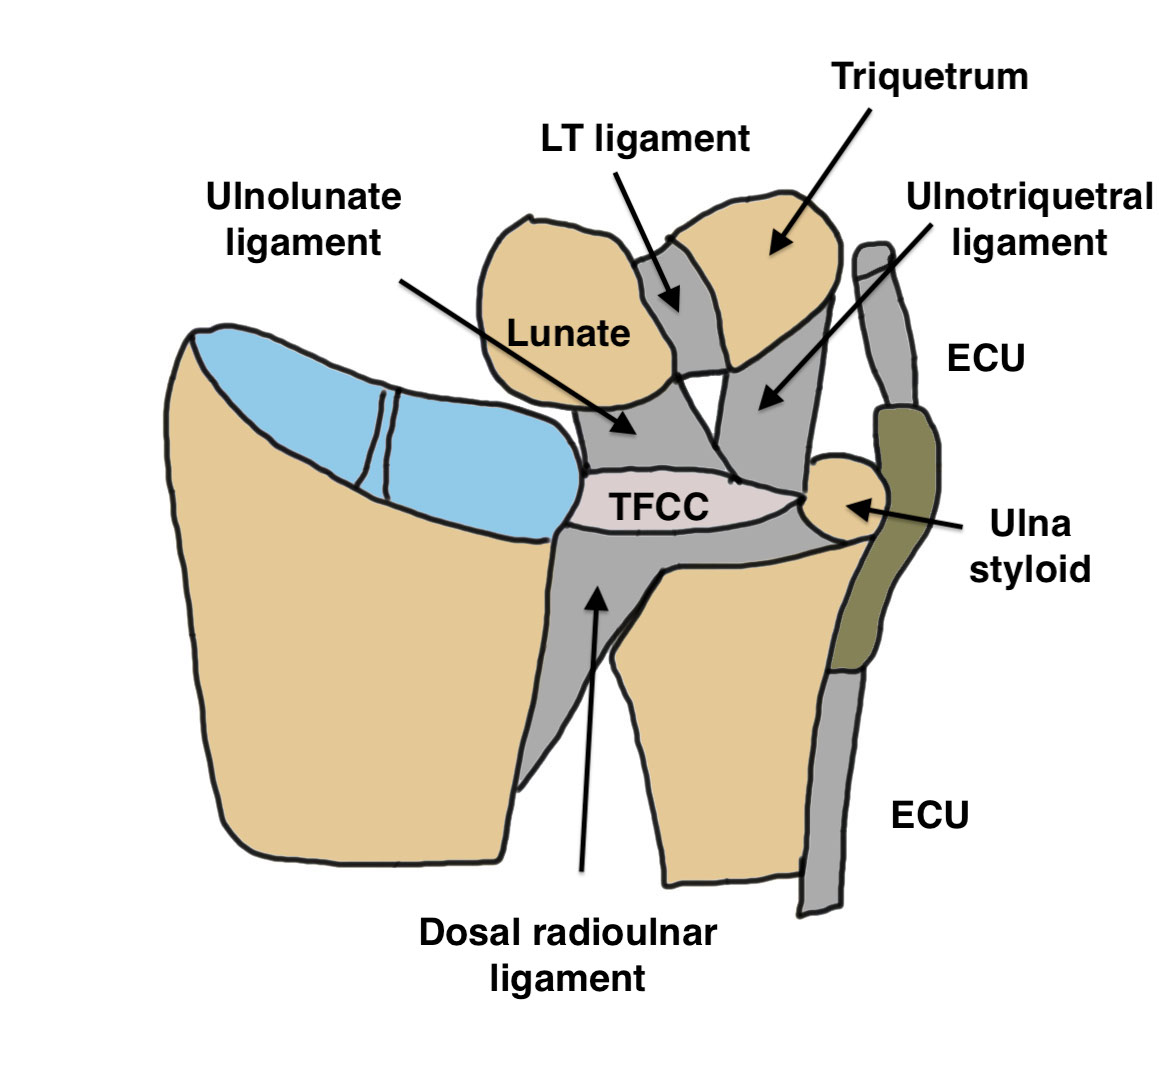

Anatomy

Ulna styloid

- bony projection from ulna

- fovea at base for soft tissue attachments

- TFCC / radio-ulna ligaments